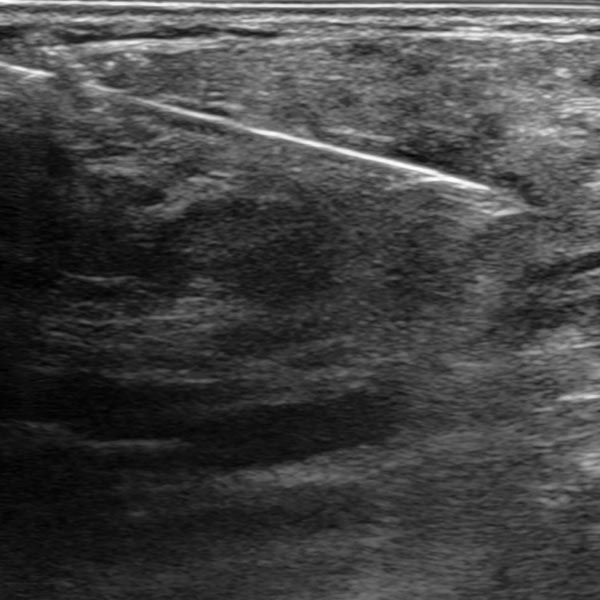

Starting from the 2nd week of life, the infant developed a total of 8 small typical, slow-growing cutaneous infantile hemangiomas. In addition, there was a circumscribed swelling ventrally in the middle of the left upper arm that was slowly increasing in size. The overlying skin was not discolored. The B-scan ultrasound shown here, at the end of the 4th month of life, reveals a relatively hypoechoic tumor in the subcutaneous tissue.

Histopathological evaluation by punch biopsy was performed in order to clearly confirm the diagnosis despite the evidence of infantile hemangioma, in view of the differential behavior of the cutaneous (almost regressed) and subcutaneous portions (re-enlargement). The ultrasound image shows the biopsy needle inside the tumor on the upper arm.